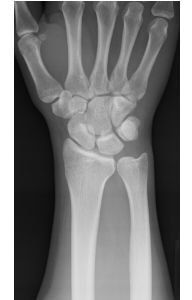

橈骨遠位端変形治癒骨折の術前(左)と術後(右)

大きな変形を残して骨が癒合すると手関節の疼痛や手指の機能障害が残存したり、将来、二次性の変形性関節症を生じる原因となることがあります。骨の変形による症状を改善させるために、矯正手術(骨切術)が必要になることがあります。

『骨折したのだから障害が残っても仕方が無い』という考え方は過去のものです。将来なるべく不自由をしないために、きちんとした診断と適切な治療を受けられて下さい。新鮮な骨折はもちろん骨折後の障害についても、お気軽にご相談下さい!